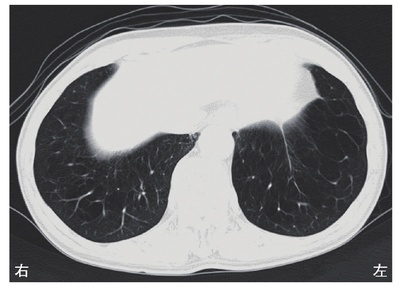

この患者は高血圧、高脂血症、糖尿病の既往歴があり、喫煙者であるため、動悸と左肩周囲の違和感を訴える原因として労作性狭心症が最も考えられる。症状が運動中止と安静により消失したことも、労作性狭心症の特徴に合致する。

労作性狭心症は、心臓への酸素供給が運動により増加した酸素需要に追いつかず、心筋虚血が生じる症状である。この患者は高血圧、高脂血症、糖尿病の既往歴があり、喫煙者であるため、動悸と左肩周囲の違和感を訴える原因として労作性狭心症が最も考えられる。症状が運動中止と安静により消失したことも、労作性狭心症の特徴に合致する。